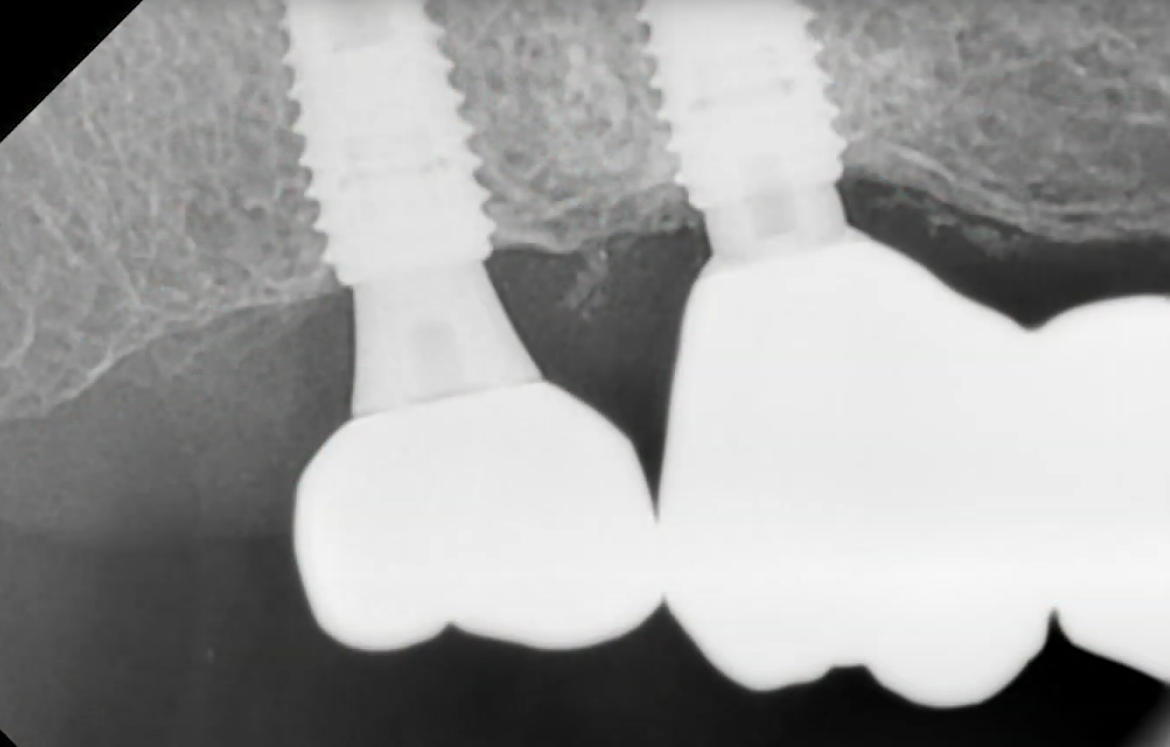

The follow-up radiograph also showed that everything was all right. The bone tissue around the implants was even in better condition after a year.

Control radiograph 12 months after restoring the previously mobile implant. YouTube/ Implantarium/ Rauf Aliyev

This is a standard outcome in such situations. In the absence of complications like inflammation or radiographic signs of pathology, the implant fully re-integrates and can provide service for decades.